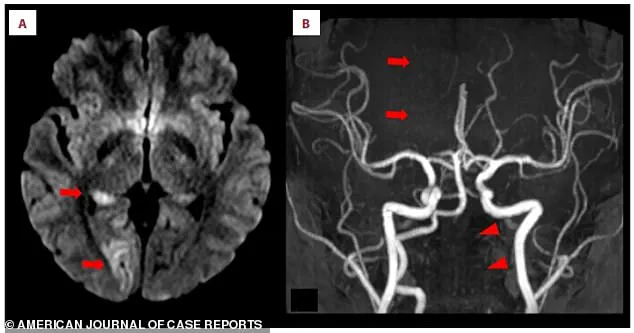

Medical imaging revealed the full extent of the damage.

In an MRI scan, bright white spots indicated acute ischemic stroke in the right occipital lobe, a sign of brain tissue deprived of oxygen.

Closer inspection of the scans showed a missing section of the right posterior cerebral artery, a critical vessel that supplies blood to the brain.

This absence pointed to a blockage, likely caused by a blood clot.

Further analysis of the left vertebral artery, a key artery in the neck that feeds the brain, showed it was faint and thin, suggesting restricted blood flow.

This discovery was a crucial clue in understanding the stroke’s origin.

The clot itself was confirmed in a second scan.

A crescent-shaped blood clot had formed inside the wall of the left vertebral artery, blocking blood flow and triggering the stroke.